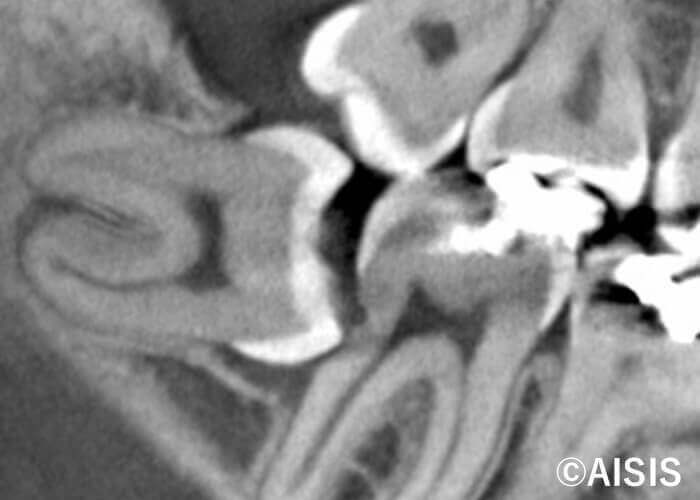

レントゲン写真は、横向きに生えている親知らずです。

親知らずが横向きに生えていることによって、手前の歯と親知らずが密接している箇所が黒ずんでいるのを確認頂けると思います。この部分が虫歯になっています。

高知市の歯医者 木口歯科医院では、必要に応じてCTレントゲンで事前に親知らずの方向を確認し、抜歯を行います。抜歯にはマイクロスコープをによる高精度の治療を行います。副院長は口腔外科での勤務経験がありますので、お困りの方は、お気軽にご来院の上、ご相談ください。